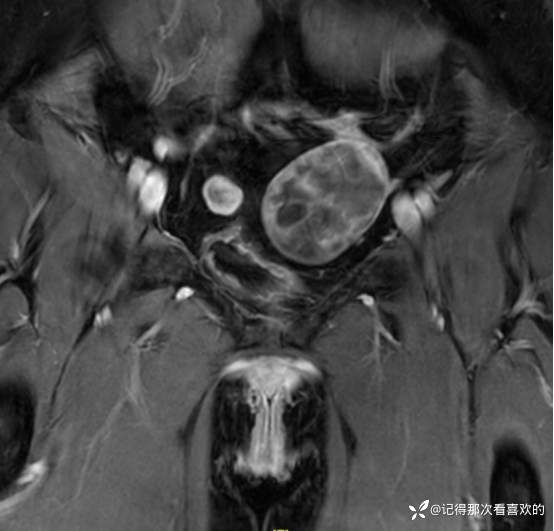

入院后查十二通道常规心电图:1、窦性心律2、逆钟向转位。余相关检验未见明显异常。于2025.05.30在静脉麻醉下行“宫腔镜诊断性刮宫术”,术顺,术后病理(2508387):(宫内容物)子宫内膜息肉。查心脏彩超(Z250530002):三尖瓣轻度反流。双侧下肢深静脉血管彩色多普勒超声(Z250530003):双侧下肢股总静脉反流,考虑双侧下肢深静脉瓣功能不全。经阴道彩超检查(Z250530004):双侧附件区低回声不均团块,考虑MT,建议进一步检查。子宫多发肌瘤。子宫内膜区低回声结节,考虑粘膜下肌瘤可能。宫颈腺体多发囊肿。盆腔MRI增强(MR109286):1.双侧附件区团块状占位,考虑MT,请结合临床。2.子宫肌层内、浆膜下多发肌瘤。3.子宫腔内异常结节灶,粘膜下肌瘤可能。4.盆腔少量积液。5.右侧髂骨内结节灶,性质待定,建议进一步检查。胸部CT(CT384707):1.双肺多发微小结节,建议随诊复查。2.气管憩室。3.扫及右肾结石?新上腹部CT平扫(CT384838):盆腔右侧占位性病变,请结合临床及MRI检查。HPV+TCT:HPV阴性;非典型鳞状上皮细胞(不能明确意义)。2025.06.03行胃肠镜,电子胃十二指肠镜检查(PG25003031):胃体溃疡(待病理);慢性萎缩性胃炎。电子结肠镜检查(PC25002608):结肠多发息肉(内镜下息肉切除+钳除)。快速石蜡病理(2508504):胃体:低分化腺癌,伴少量印戒细胞癌成分,免疫组化结果待补充报告。快速石蜡病理(2508505):降结肠:增生性息肉。